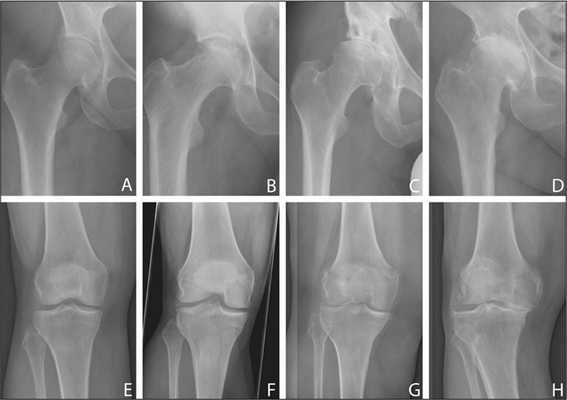

- деформирующий остеоартроз (коксартроз) 3 стадии по классификации Кассинской или 4 по классификации Kellgren J. H., Lawrence J. S.; ;

- деформирующий остеоартроз (гонартроз) третьей стадии; ;

Динамика болезни на рентгене.

Откладывать хирургию при гонартрозах 3-4 степени чревато деформацией позвоночника. Это происходит из-за хромоты. Дегенеративные процессы артроза глубоко затронут кости, из-за чего они приобретут хрупкость, потеряют плотность и зафиксировать к ним компоненты импланта станет сложно.